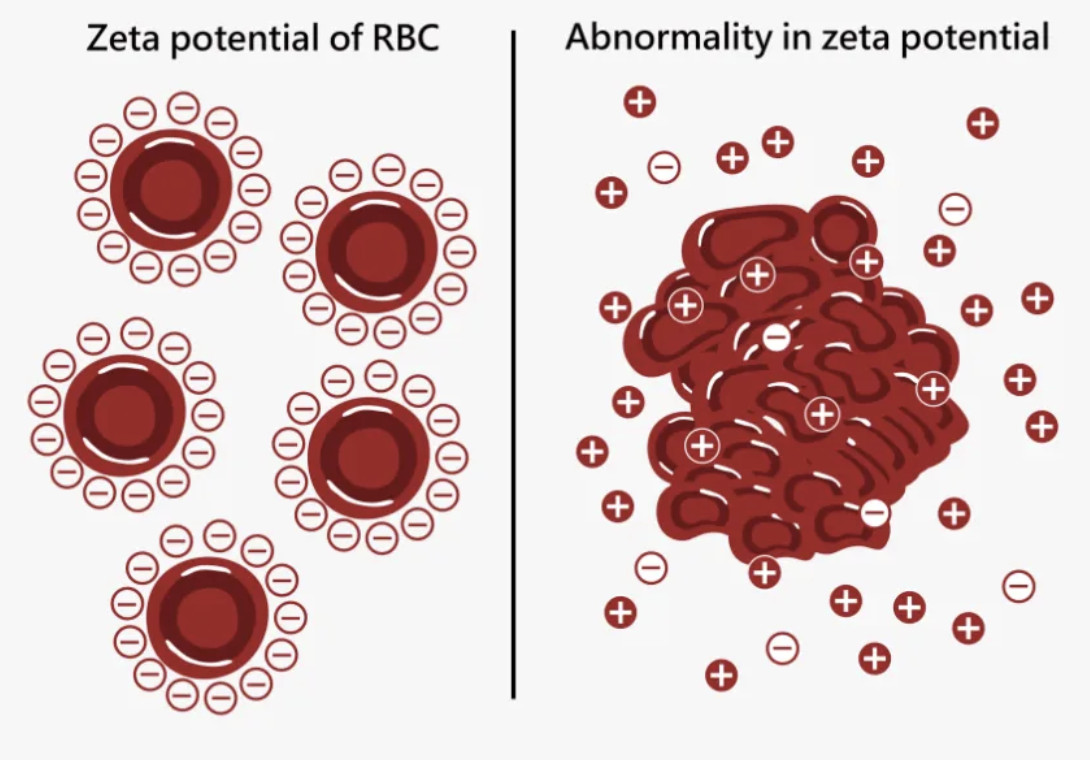

Another concept I've emphasized throughout this publication is zeta potential, which quantifies the electrical charge difference between colloidal particles in the liquid they are suspended within (and applies to most fluids systems in nature). This is because like charges repel each other, so when a sufficient amount of matching charges are present (which in nature are almost negative due to liquid crystalline water creating a negatively charged layer on what it coats), the particles in the solution will resist outside pressures (e.g., gravity or attracting charges) to clump together and instead stay dispersed. Conversely, when insufficient zeta potential is present, they will clump together, with the clumps becoming larger and larger as the zeta potential declines.

In the body, if this happens, red blood cells will clump together, eventually forming microclots which can cause either acute illness, or more commonly chronically debilitating illnesses. For example, in the previous article, I showed the extensive proof vaccines frequently injure patients by triggering microstrokes by disrupting the physiologic zeta potential.

In turn, we believe this process underlies many chronic illnesses as agents that are well suited for restoring it often create dramatic improvements in health (which numerous readers here have reported) while conversely agents that are well suited for disrupting it (e.g., aluminum, the spike protein, and dangerous microbes such as malaria) can often cause a myriad of challenging illnesses.

However, as these fail, it begins becoming possible for compressive forces to collapse the veins. Since hypermobility weakens the lining of the blood vessels, in practice, we find hypermobile patients have a reduced ability to tolerate impairments of the physiologic zeta potential or the liquid crystalline water within it (as the strength of the blood vessel linings can no longer adequately compensate for a loss of the expansive forces within the vessels), and as such, they often far more frequently pass a critical zeta potential threshold where issues immediately follow.